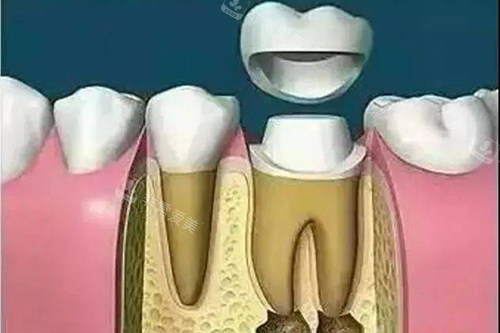

热牙胶充填系统:热牙胶充填系统可以使根管充填更加严密,有效防止细菌再次侵入根管。

这种靠前的充填技术能够更好地保存患牙,延长牙齿的使用寿命。